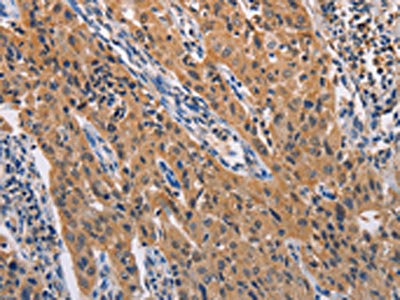

The image on the left is immunohistochemistry of paraffin-embedded Human lung cancer tissue using CSB-PA023292(ADAMDEC1 Antibody) at dilution 1/20, on the right is treated with fusion protein. (Original magnification: ×200)